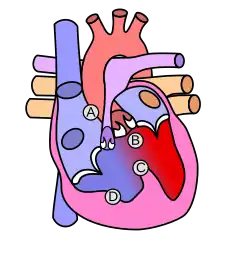

B: überreitende Aorta, C: Ventrikelseptumdefekt, D: Rechtsherzhypertrophie |